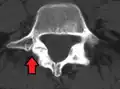

Anterolisthesis L5/S1 -

Anterolisthesis L5/S1. Blue arrow normal pars interarticularis. Red arrow is a break in pars interarticularis. -

Anterolisthesis L5/S1